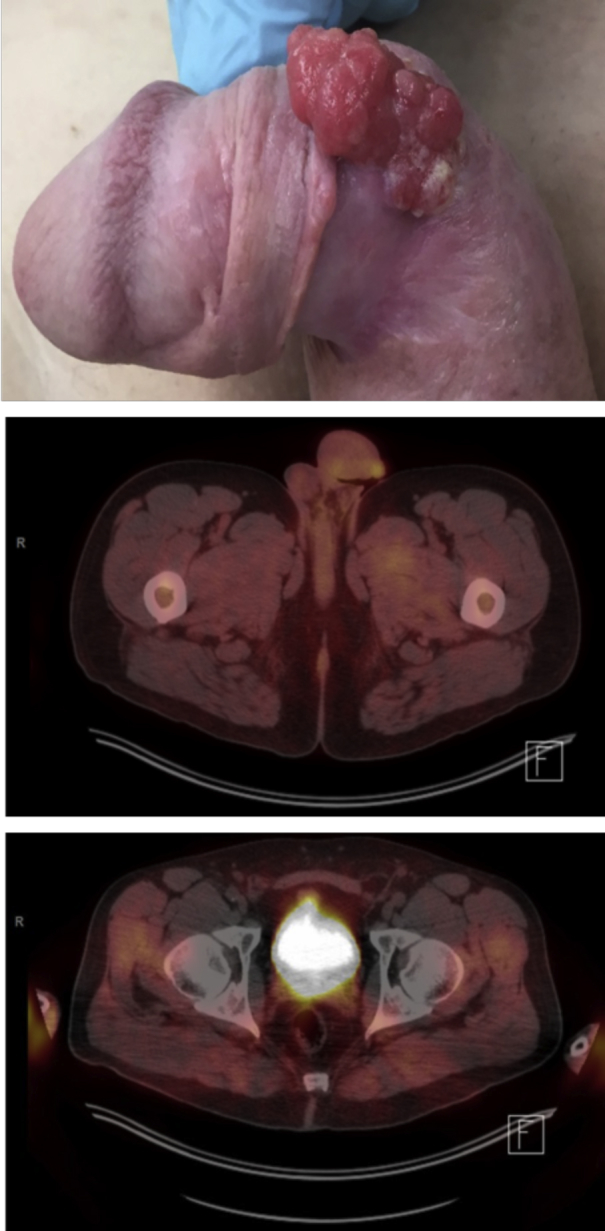

Fig. 1.

Primary tumor and lymphadenopathy at time of diagnosis (Photo and PET Scan).

A 46-year-old man presented with biopsy proven invasive keratinizing SCC of the penis, with clinical and radiographic evidence of concurrent inguinal lymphadenopathy. He sought a second opinion after being advised he would require a complete penectomy and perineal urethrostomy by an outside provider—he was unwilling to consider treatment that would demand loss of his penis. Physical examination revealed a large, draining, ulcerated and nearly circumferential penile mass, covering the bulk of the ventral and lateral surfaces (Fig. 1). Multiple left-sided (largest 2cm) inguinal lymph nodes (LNs) and shoddy, non-specific right-sided LNs were palpable. Evaluation by F18-FDG PET/CT was performed, and the primary tumor and bilateral inguinal LNs were positive; needle biopsy of the left inguinal LN confirmed metastatic SCC (Fig. 1). Per National Comprehensive Cancer Network guidelines for AJCC Stage IIIb disease (cT1N2M0; Grade 2), NAC was offered,2 with deferral of treatment of the primary tumor. Four cycles of TIP were administered and well tolerated with minimal toxicity, and we observed a complete response in the LNs on repeat F18-FDG PET/CT (Fig. 2). Additionally, NAC resulted in a profound primary tumor response with significant regression (Fig. 2). Subsequently, he proceeded with consolidative surgery and the residual penile mass was removed by wide local excision with the surgical defect reconstructed by use of full thickness skin graft; he also underwent bilateral inguinal LN dissection to obtain complete pathologic staging. No gross invasion of the corpora or spongiosum was noted intra-operatively (Fig. 3). Final surgical pathology demonstrated no residual cancer in 16 inguinal LNs and a 2.8 cm residual superficial invasive carcinoma of the penis (AJCC Stage 1: ypT1aN0M0, Grade 2). He has fully recovered, retaining his baseline voiding function, and he reports no change in sexual function. MRI of the pelvis performed 8 months post-operative reveals no evidence of disease.